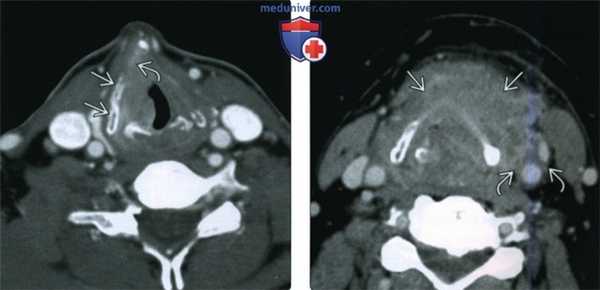

(Слева) При аксиальной КТ с КУ в преддверии гортани визуализируется объемное образование, смещающее жировую ткань. Его часть, не накапливающая контраст и имеющая плотность, соответствующую слизистому компоненту, представляет собой внутреннее ларингоцеле, возникшее в результате обструкции желудочка гортани опухолью.

(Справа) При аксиальной КТ с КУ у этого же пациента, выполненной каудальнее, визуализируется опухоль (плоскоклеточный рак), полностью вовлекающая окологортанное пространство. Пластинка щитовидного хряща склерозирована, но признаков ее деструкции нет. Подподъязычные мышцы ниже уровня подъязычной кости слева не выглядят измененными, признаков распространения опухоли за пределы гортани не выявлено (стадия Т3).в) Дифференциальная диагностика плоскоклеточного рака преддверия гортани: